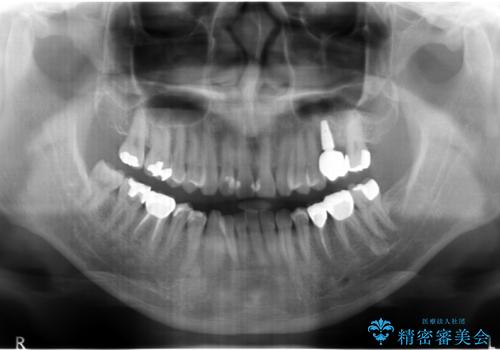

上の奥歯のインプラント、全体的な虫歯治療

- 上の奥歯が無いところにインプラントを希望して来院。

インプラントの向かい合わせの歯や隣の歯の虫歯治療も併せて行なっています。

治療の内訳

左上6:インプラント(ストローマン)20万円、カスタムアバットメント10万円、スクリューリテイン仮歯2万円、ジルコニアクラウン10万円、ソケットリフト10万円、マイナーGBR 5万円、静脈麻酔(麻酔認定医)5万円

左上7・左下7:PGAインレー 各6万円

左下5:仮歯 1万円、ジルコニアクラウン10万円、ファイバーコア 2万円

左下6:仮歯1万円、ジルコニアクラウン10万円

クラウンは全てスタンダードです。